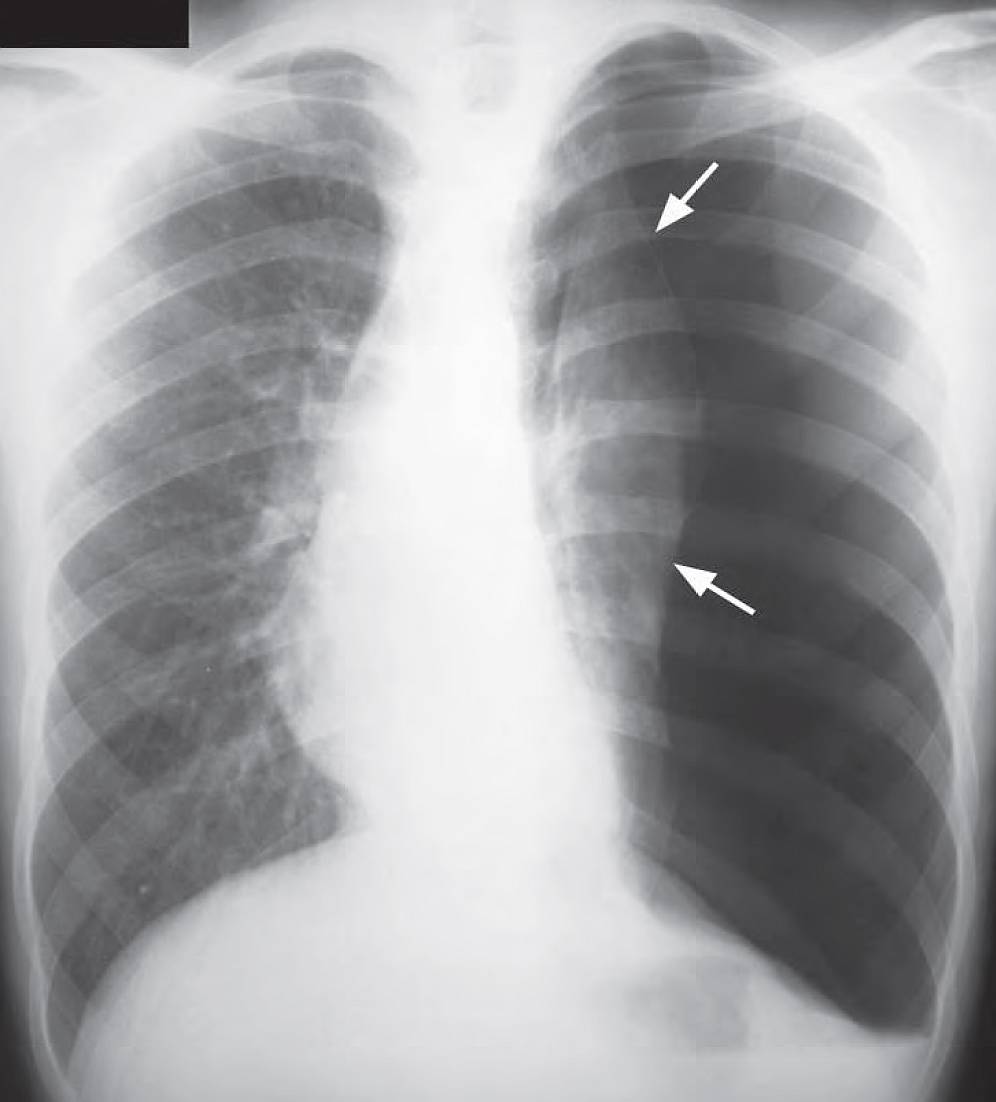

This post is an answer to the Case – Sudden Left Sided Chest Pain and Dyspnea

Chest X-Ray Interpretation

- Hyperlucent zone devoid of vascular marking in periphery of left hemithorax.

- Shift of midline to the right.

Diagnosis

Large left pneumothorax with mediastinal shift to the right.